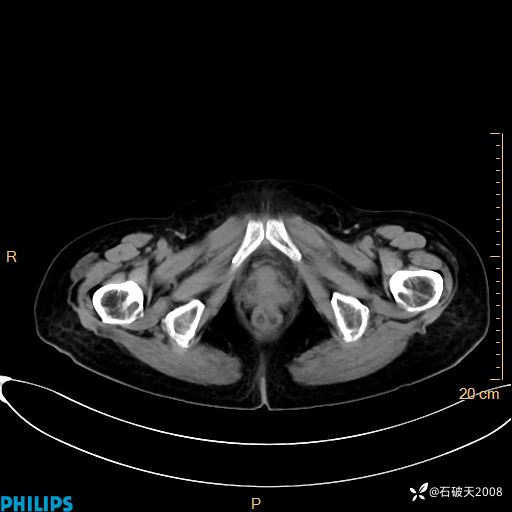

平扫

动脉期

MIP

静脉期